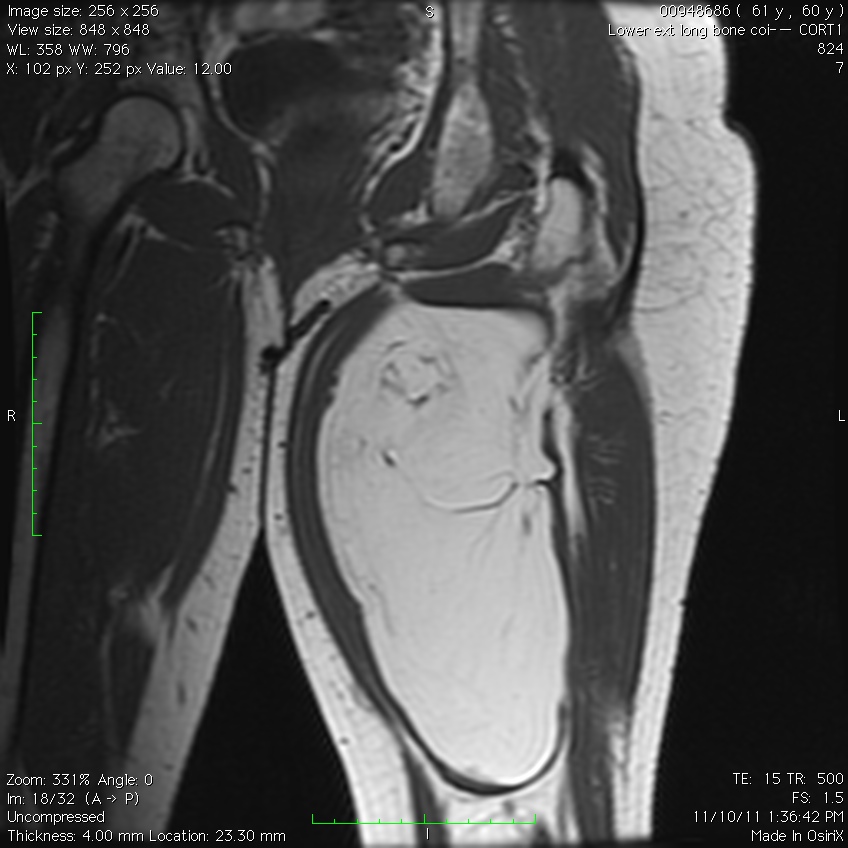

MRI

• Follows the signal characteristics of subcutaneous fat on all sequences

• T1: High Signal

• T2: Intermediate Signal; Low Signal with Fat Suppression

• Minimal or No enhancement with gadolinium

Fig. 1A, 1B, 1C, 2A, 2B, 2C: MRI of a lipoma: T1- weighted images shows an homogeneous mass in the posterior compartment of the thigh with high signal, saturates on fat saturated sequences with no or minimal enhancement. On T2-weighted images demonstrate an intermediate signal on FSE T2, saturates (becomes dark) on fat saturated sequences.